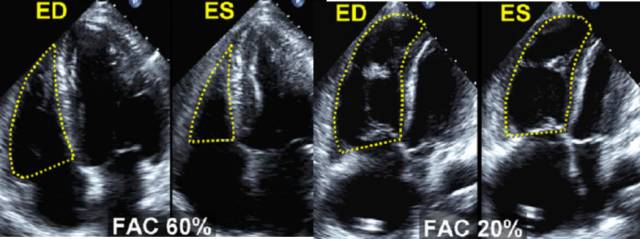

9、右室收缩功能的测量

面积变化率(FAC)=100*(EDarea-ESarea)/EDarea。

FAC<35%提示右心室收缩功能降低